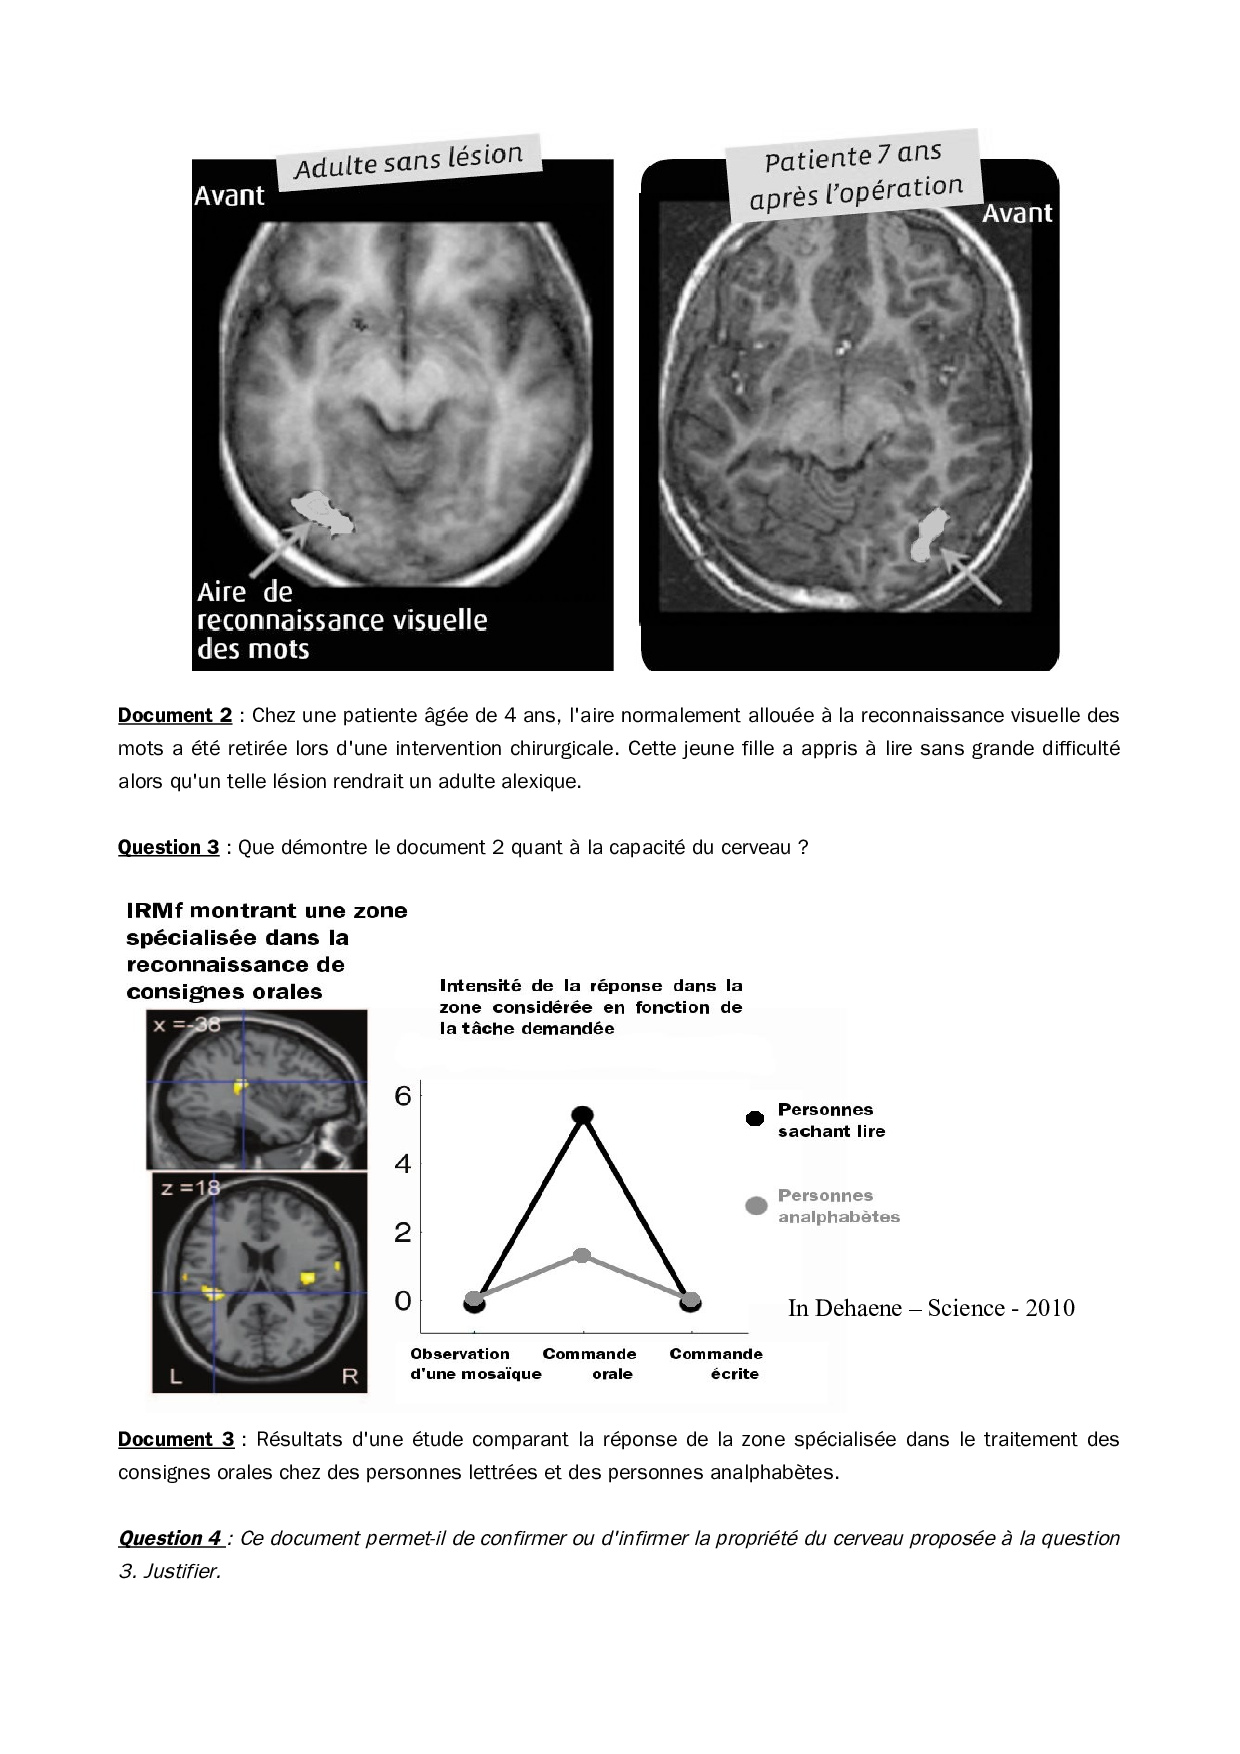

Représentation visuelle - Activité 7 (La plasticité cérébrale)